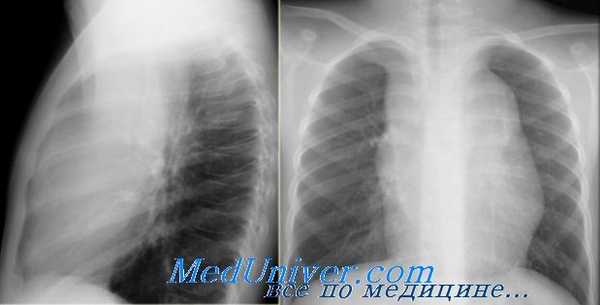

Но случаются ситуации, когда мы не видим никаких изменений, как на обзорной рентгенограмме в данном случае: практически легочные ткани. Но, посмотрите – корень левого легкого располагается на одном уровне с корнем правого легкого. Это позволяет нам предположить, нет ли тут какого-то процесса, который приводит к уменьшению объема.

На боковой рентгенограмме мы видим ателектаз язычковых сегментов, который в данном случае скрыт за тенью сердца. Именно этот процесс и вызывает смещение корня легкого.